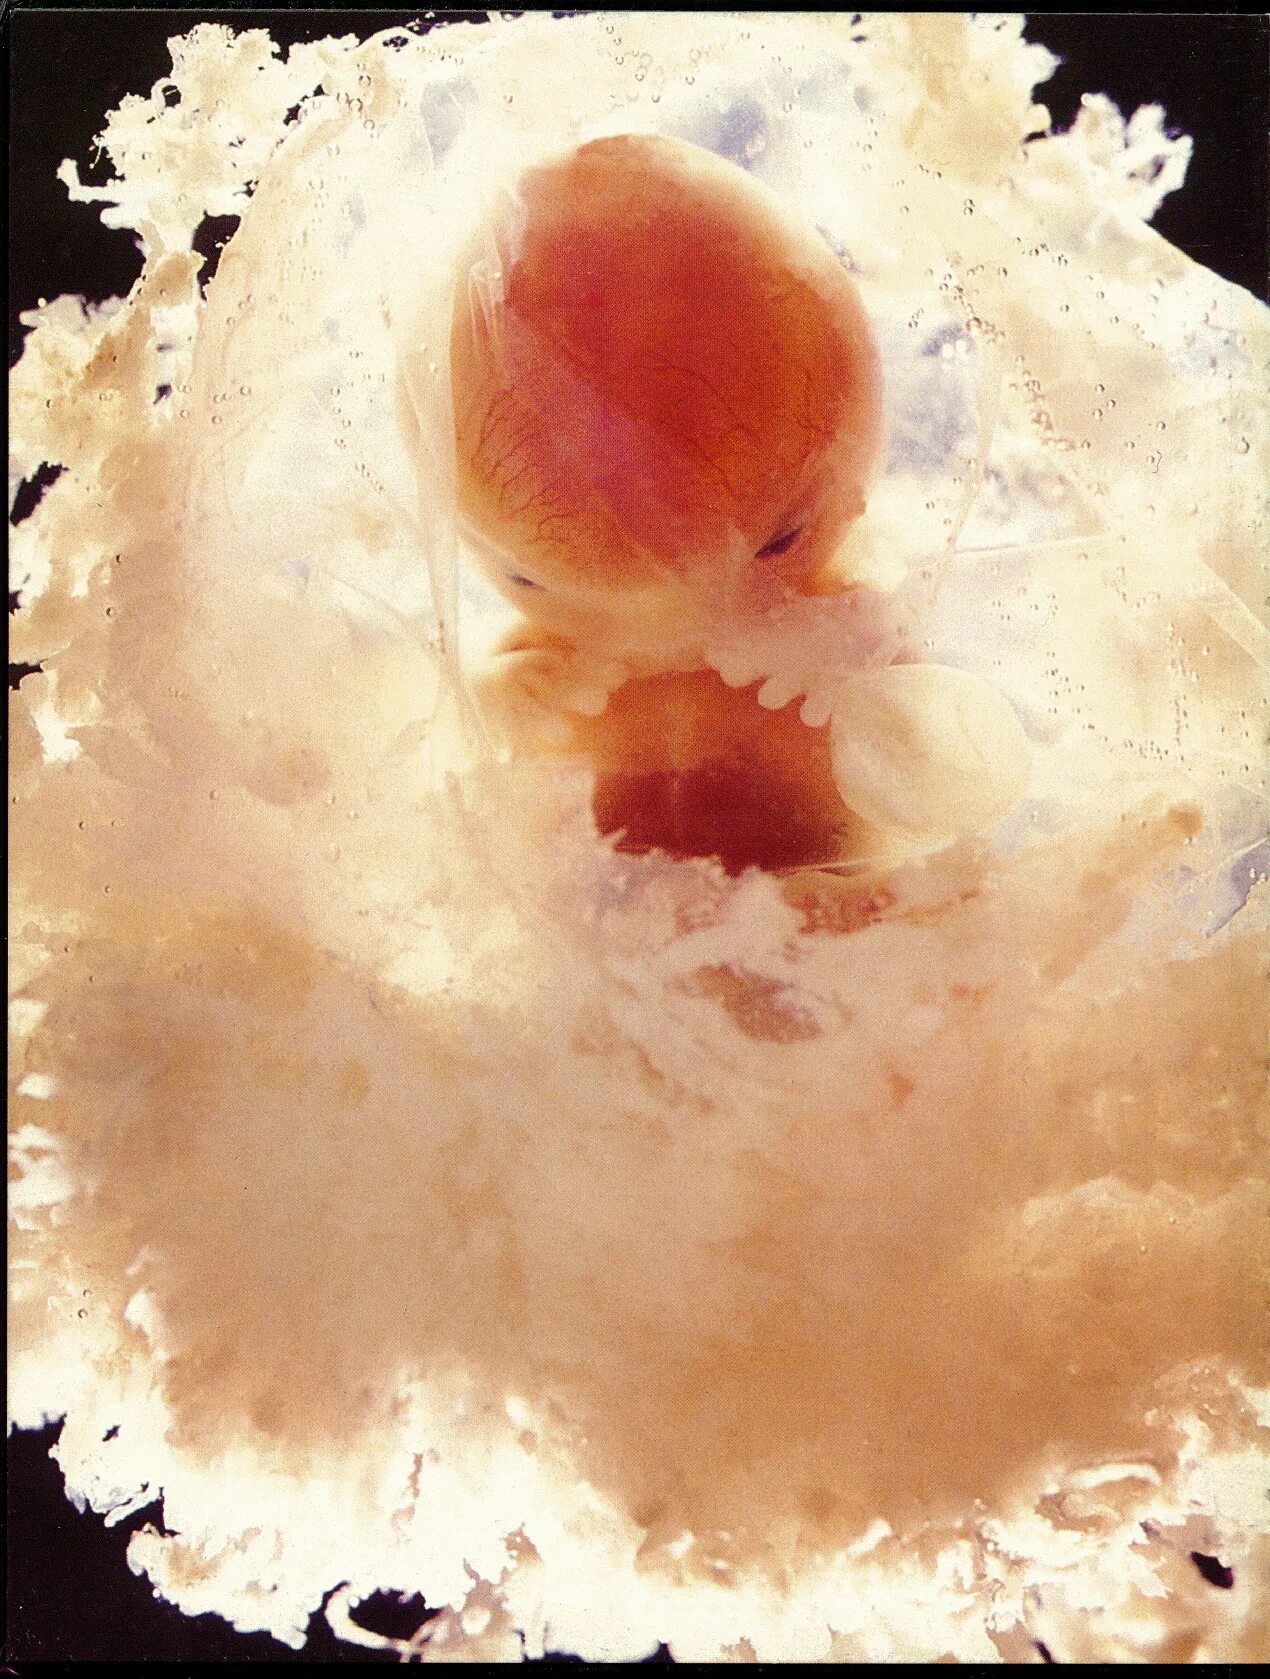

Коричневая мазня при беременности на ранних сроках беременности.7 недель после узи выделения. выделения при беременности 7 недель. выделения на 7 неделе беременности. выделения по неделям беременности.Коричневые выделения при беременности. коричневая мазня на 6 неделе. светло коричневые выделения на 6 неделе.7 недель беременности фото плода на узи. узи на 7-8 акушерской неделе беременности. фото эмбриона в 7 недель беременности фото узи. узи 7 недель беременности узи.Коричневая мазня на 7 неделе. коричневая мазня на 6 неделе беременности. коричневые выделения на 7 акушерской неделе.Коричневые выделения на 6 неделе беременности. выделения на 6 акушерской неделе. коричневые выделения 13 акушерская неделя беременности. 7 недель мажется коричневым.Выделения на 6 акушерской неделе. выделения на 6-7 неделе беременности норма. коричневые выделения на 6 неделе. коричневые выделения на 7 неделе.Узи беременности на ранних сроках. замершая беременность узи. беременность на узи до задержки. узи замершей беременности на ранних сроках.Узи на 7 акушерской неделе беременности. 7 неделя беременности акушерская узи узи. узи 7 недель беременности акушерская фото плода. плод на 7 неделе беременности узи.Эмбрион на 7 акушерской неделе. плод 7 недель беременности размер плода. эмбрион 6-7 недель как выглядит. размер ребенка в 7 недель.Признаки ретрохориальной гематомы при беременности 6-7 недель. узи беременности на ранних сроках.Беременность на ранних сроках. выкидыш по срокам беременности.Мазня на пятой акушерской неделе. коричневые выделения на 7 акушерской неделе. узи 7-8 недель беременности. беременность на ранних сроках 5 недель.Выделения срок 7 недельРетрохориальная гематома на 7 неделе беременности. узи 7 недель беременности гематома. гематома при беременности на ранних сроках. ретрохориальная гематома на узи.Размер ребенка на 7 неделе беременности. размер эмбриона на 7 неделе. плод 7 недель беременности размер плода.При беременности на ранних сроках. мазня при беременности до задержки. беременность выделения до задержки. выделения при беременности на ранних сроках после задержки.Плодное яйцо 6 недель по узи. плодное яйцо 7 недель узи. плодное яйцо 5 недель на узи беременность 6.Коричневатые выделения при беременности. слизистые коричневатые выделения при беременности. коричневатые выделения на ранних сроках беременности. темные коричневые выделения.Выделения срок 7 недельВыделения срок 7 недельЗаключение узи 7 недель беременности. 6 недель беременности по узи. узи беременности 4-6 недель. эмбриональный срок 5 недель узи.Выделения срок 7 недельКоричневые выделениепри беременности. мажущие коричневые выделения. светло коричневая мазня.Коричневатые выделения. светло коричневые выделения. светло желтые выделения.Узи на 2-4 недели беременности. узи беременности на ранних сроках. узи по беременности на ранних сроках.Светло бежевые выделения. желто бежевые выделения. светло розоватые выделения.Розово бежевые выделения. бледно розовые выделения на ранних сроках. бежево розовые выделения при беременности.Выкидыш на ранних сроках беременности. выкидыш на 6 неделе беременности. зародыш на 4 неделе выкидыш.Ведетентя при беременности. бледно коричневые выделения.Выделения на 5 неделе беременности. кровотечение на 5 неделе беременности. кровомазание на 6 неделе беременности. кровит на раннем сроке беременности.Выделения срок 7 недельКоричневатые выделения. выделения прибеременосьи. светло бежевые выделения.Выделения срок 7 недельИмплантационное кровотечение. мажущие кровянистые выделения. кровянистые розовые выделения.Светло коричневая мазня. светло бежевые выделения. небольшие розовые выделения.Темнокорияневве выделения. темно коричневые выделения. темные коричневые выделения.Узи 7 недель беременности гематома. гематома на узи при беременности. ретрохориальная гематома узи заключение.Выделения срок 7 недельРозово бежевые выделения. светло бежевые выделения. выделения розового цвета.